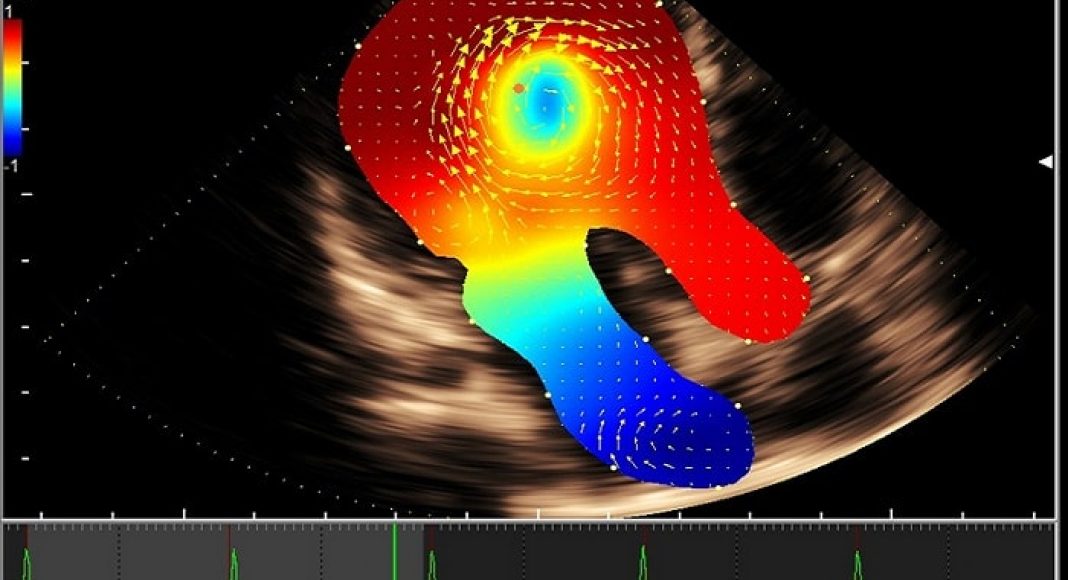

Hitachi Medical Systems Europe introduced what it calls the next level of intelligent Vector Flow Mapping (iVFM) at EuroEcho Imaging 2018, Dec. 5-8 in Milan, Italy.

The third generation of Hitachiβs non-invasive intracardiac blood flow visualization technology provides unique information about the intraventricular vortex and its energetic efficiency, including kinetic energy loss, relative pressure, or wall shear stress display and analysis.

Built on the premium 2-D/4-D/4G CMUT Lisendo 880LE ultrasound system as part of the HDAnalytics CV analysis package, the new iVFM features faster data processing through automation for a simplified workflow. The embedded iVFM is now available for both intracardiac and vascular flow structures.